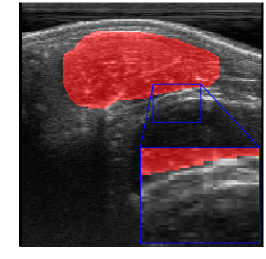

Rib Eye Area (REA). This image dataset consists of ultrasound images of the Longissimus dorsi muscle between the 11th and 13th ribs of cattle. The goal is to automatically calculate the rib eye area (REA), an important region for decision making during cattle breeding. The main challenge is the uncertainty in the REA annotation, since the image is noisy and even experts have difficulty in delimiting the borders of this region. Fig. 3 presents examples of images and the annotation made by a specialist. We can observe that some borders are absent and depend on the subjectivity and knowledge of the annotator. To evaluate the segmentation methods, 76 images with 309×213309213309\times 213 resolution were obtained and labeled by an expert. Due to the number of images, the division of the images in training and testing followed 5-fold cross-validation.

Refer to caption

Figure 3: Sample images from Rib Eye Area (REA) dataset.

REA dataset. This image dataset has high uncertainty during labeling due to noise from the ultrasound image. In some cases, the border of REA is not completely visible and must be estimated by the specialist. Therefore, the proposed approach becomes essential to obtain accurate segmentation at the edges. The segmentation examples in Fig. 6 show that the baseline was not able to define the REA correctly due to the uncertainty of the labeling. On the other hand, the proposed approach presents results close to the specialist in regions that the border needs to be estimated.